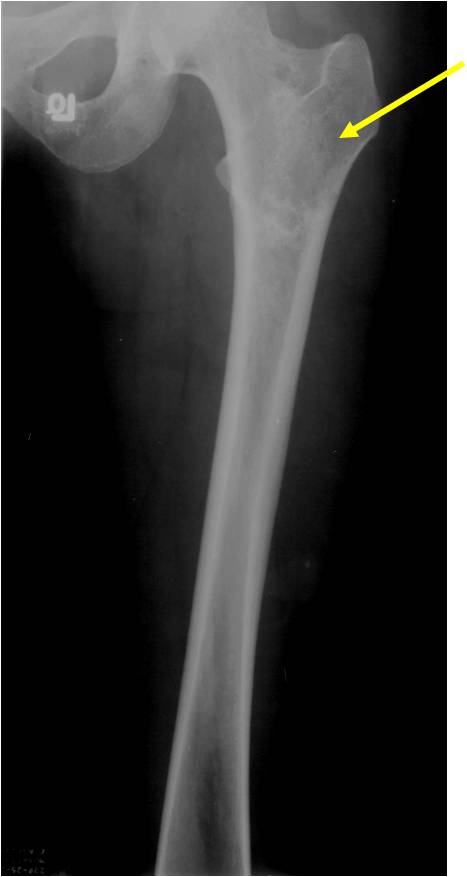

- Proximal Humerus, Femur most common long bones

- Most commonly found in metaphysis

- Geographic lytic lesion

- Central often metaphyseal in long bones

- Expansile remodeling with thinned cortex

- Chondroid matrix with calcifications in majority of tumors

- Endosteal scalloping and cortical expansion is acceptable for phalangeal tumors. In most benign long bone cartilage tumors there is minimal endosteal scalloping but there should be no cortical expansion nor thickening. There should be no cortical destruction and no soft tissue component associated with an enchondroma. Cortical destruction, periosteal thickening, cortical expansion and a soft tissue component indicates a chondrosarcoma of the long bone.